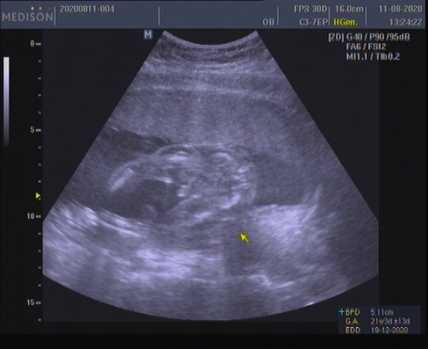

@sarlotka18 Ano, řekli mi na 90 % kluk a potvrzuje se to (jsem 28tt) 🙂. Přikládám i foto 🙂.